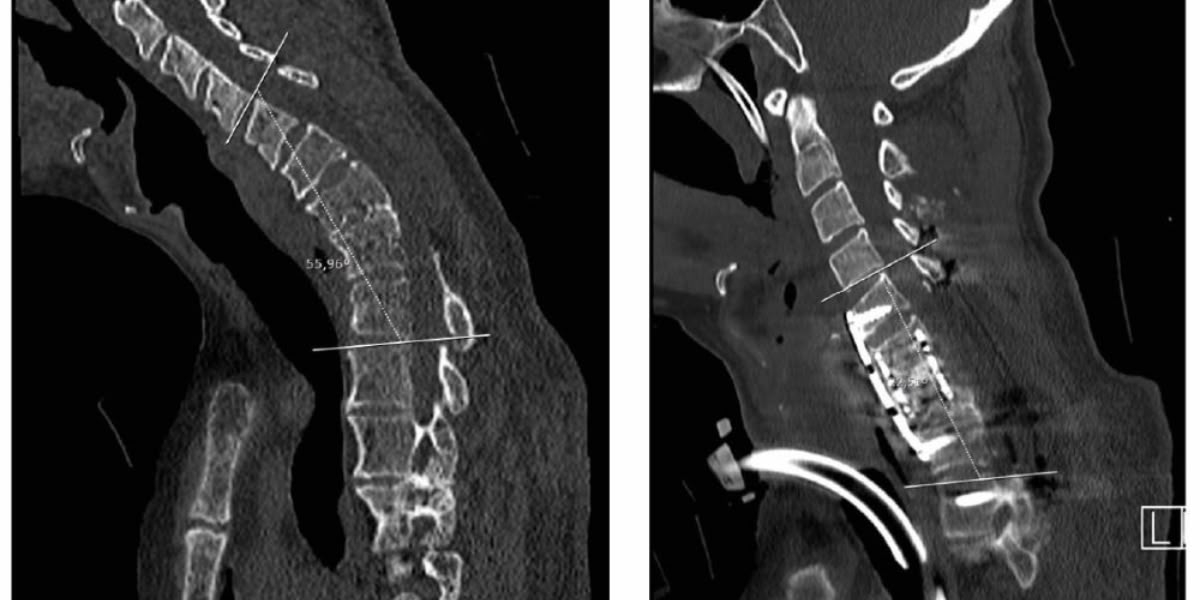

Degut a la complexitat del cas -les vèrtebres cervicals són més petites i el pacient ja havia estat operat prèviament- l’equip de neurocirurgians va decidir realitzar una operació quirúrgica amb l’objectiu de corregir la corba de 56º i fixar la posició de la columna.

Segons explica el Taulí, per poder fer aquesta operació, primer es va fer una planificació amb un model anatòmic tridimensional, amb l’ajuda del Tailor Surgery, on es va dissenyar la trajectòria dels claus a través de la vèrtebra per no lesionar les artèries vertebrals i la medul·la cervical. Posteriorment, es van dissenyar unes guies personalitzades que es van posar en les estructures fixes del pacient, per poder col·locar correctament els claus. L’operació va ser un èxit, es va aconseguir corregir més de 33º la cifosi prèvia fixant el coll del pacient en una posició pràcticament normal, de 20º.